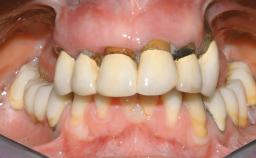

Immediate Loading of Eight Implants in the Maxilla and Six Implants in the Mandible and Final Restoration with Three-Unit and Four-Unit FDPs

Extensive scientific evidence has confirmed that immediately loaded implants with fixed full-arch provisional restorations can osseointegrate with success rates similar to conventionally or delayed loaded implants. A number of immediate-provisionalization techniques for edentulous jaws have been described. Some protocols differ when it comes to prefabricated provisional templates versus complete denture conversion; intrasurgical impressions versus direct relining; and cemented versus screw-retained provisional restorations. In this context, complete-denture conversion has been proposed for either intrasurgical impressions or direct relining. Another possibility is the utilization of a prefabricated provisional to be adapted either in the mouth (by direct relining) or in the laboratory (on a working model obtained from an intrasurgical impression).

Case Type Edentulous Maxilla

Defining Characteristics Fully edentulous upper jaw to be rehabilitated with four or more implants